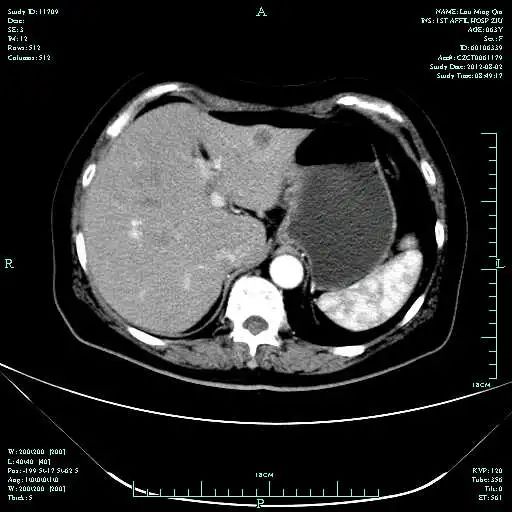

基于ToGA研究结果、以及我国曲妥珠单抗胃癌适应症获批,进行下一步治疗:外院胃镜切片标本再会诊:HER2 IHC +++

疗效评估:cPR

TOGA研究是第一个使用HER2抑制剂曲妥珠单抗治疗不能手术的局部晚期、复发或转移的HER2阳性胃癌患者的Ⅲ期临床研究。TOGA研究结果显示,IHC2+/FISH阳性或者IHC3+的患者与对照组相比,OS分别为16.0个月和11.8个月(HR为0.65)。曲妥珠单抗联合化疗显著提高了HER2阳性晚期转移性胃癌的治疗缓解率和总体生存率。2012年8月,曲妥珠单抗治疗HER2阳性转移性胃癌适应症在我国获批。对该患者进行病理切片会诊,幸运的是其HER2检测为阳性。随即进行靶向联合化疗治疗,三个周期后,肝转移灶消失,曲妥珠单抗治疗效果显著。九个周期的靶向治疗联合放化疗后,疗效评估cPR,随即行手术治疗。